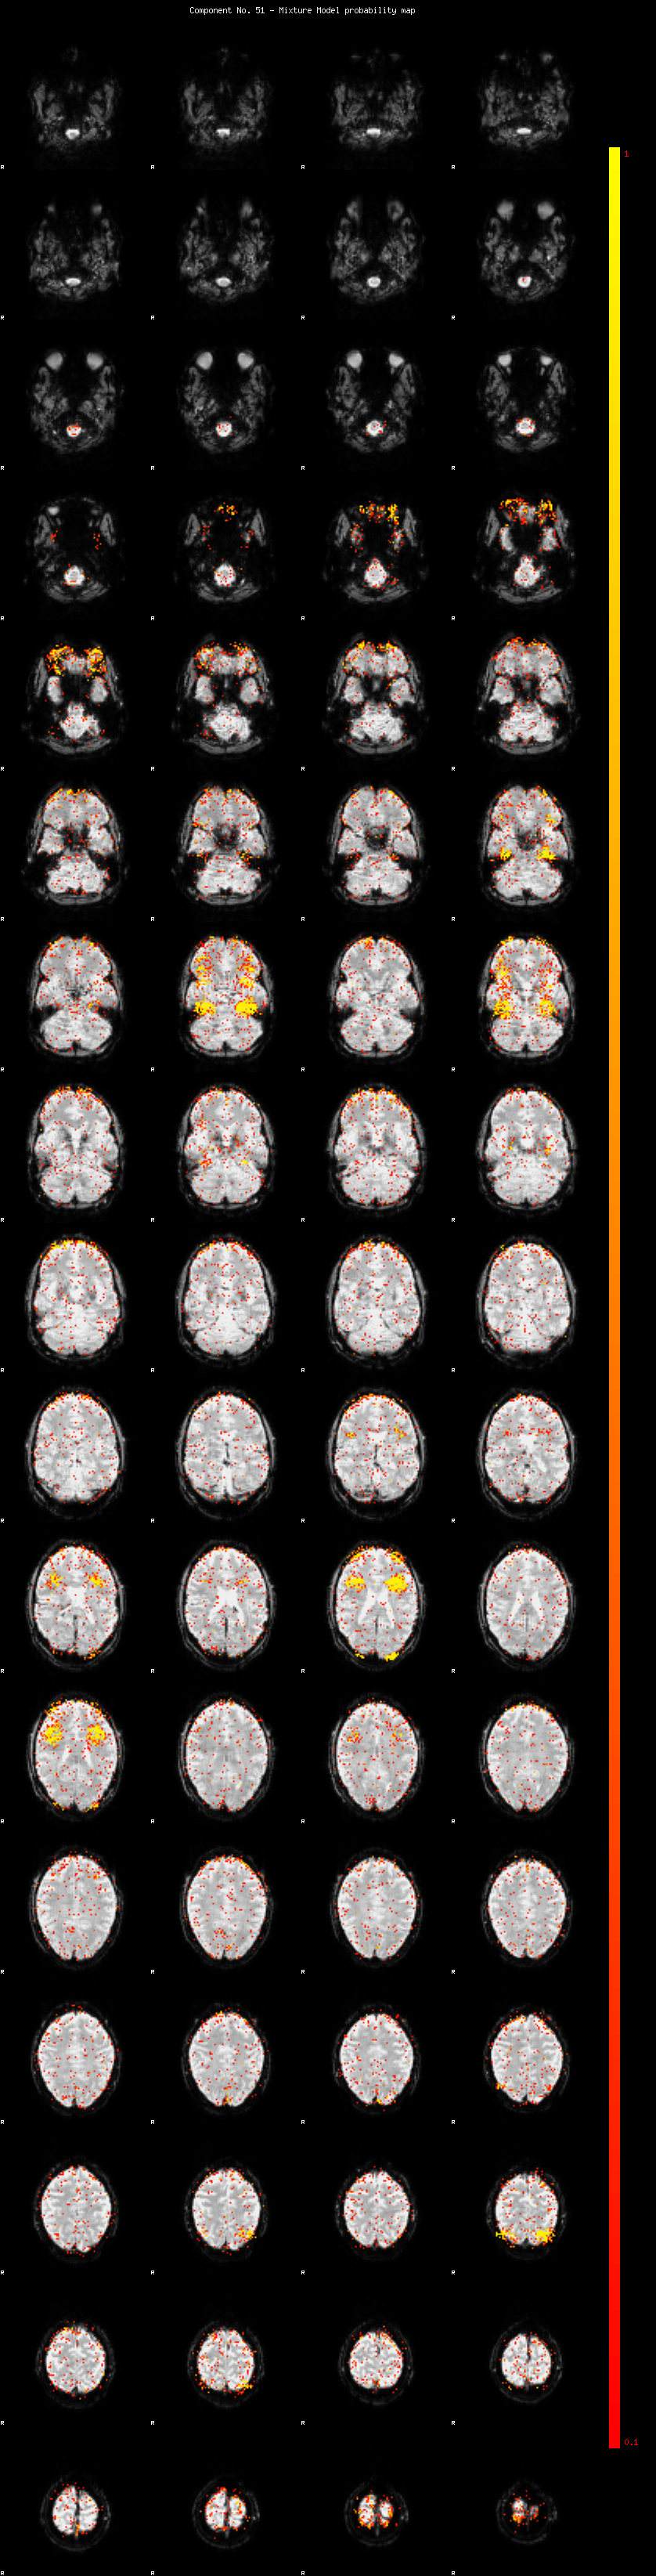

IC_51 Mixture Model fit

Means : 0.000000 2.646792 -2.650260

Vars : 1.000000 2.628951 2.679984

Prop. : 0.954702 0.024014 0.021284